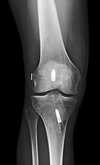

patellar tendon rupture repair options and outcomes, most common complication, most important prognostic factor

*Suture anchor tendon repair*: atleast 2 achors, **higher ultimate load to failure and less gap formation compared to transosseus fixation.** Transosseus repair: not as good, see image outcomes biomechanical studies have shown **less gap formation with suture anchor repair** compared to transosseous repair; clinical studies have shown** a significant decrease in re-rupture rate with use of suture anchor compared to transosseous repair.** complication: #1 **knee stiffness** MUA if flexion less than 120 at 6-12 weeks post op Lyssis of adhesion if less than 120 after 12 weeks post op #2 Quadatrophy: does not compromise return of strength most important prognostic factor for complete tears is ** timing of repair**